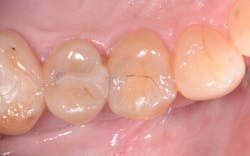

The placement of posterior composites has often troubled dentists. They can be time-consuming, technique-sensitive, and costly to do. There are a number of composites on the market that claim to be "bulk fill," implying we can reduce or eliminate multiple increments of applications. If that's the case, we would be able to tackle our operative dentistry more efficiently and more predictably. Fortunately, some bulk fill composites are "true" bulk fill composites that have the necessary ingredients to deliver on that promise. Let's look at the trials and tribulations of placing posterior composites and compare them to using Tetric EvoCeram Bulk Fill.

First, we need to consider how much time it takes to do a posterior composite. Posterior composites require a layered incremental curing strategy. Each layer can only be 2mm thick and needs to be cured for 10-20 seconds per layer. Due to the patented Ivocerin initiator with Tetric EvoCeram, you can fill up to 4mm with one placement and cure this for 10 seconds to get complete cure to the depth of the preparation. That is a time savings of 30-60 seconds per tooth. While for one tooth this may not seem like a lot, it quickly adds up when you start doing quadrant dentistry.

The stress relievers that are part of the new filler technology mean I am putting less stress on the composite, which leads to a number of advantages as well. Postoperative sensitivity is decreased due to less stress on the tooth. Also, the margins do not get the dreaded white line, indicating the bond is breaking down from too much shrinkage.

Okay, you're probably wondering, "If it cures so quickly, am I going to have to rush to get it done?" Not so. The special light filter means ambient light will not prematurely set the material. Also, the material is easy to adapt to the preparation, so placement time is reduced in trying to shape the anatomy. The ease of sculpting means less time refining anatomy and polishing, which again shaves off those precious seconds that add up to a big time savings.